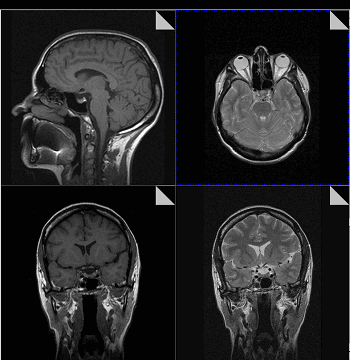

Существенное преимущество МР-томографии перед КТ заключается в том, что она не противопоказана беременным во II и III триместре и совершенно безопасна для детей. В МРТ исследуемая область сканируется в трех проекциях, что позволяет врачу-рентгенологу в полной мере оценить состояние тканей и органов исследуемой области, а высокая контрастность изображения и пространственное разрешение позволяют визуализировать серое и белое вещество головного мозга, оценивать состояние костного мозга и мягких тканей различной локализации. Кроме того, метод МРТ позволяет получать изображения сосудов головного мозга и сосудов шеи без введения контрастного препарата.